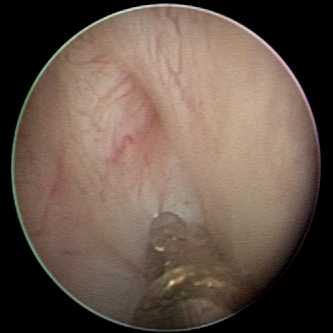

Метод ЭКР имеет множество технических нюансов, поэтому и результаты его применения значительно различаются. В настоящее время общепризнанными считаются методики STING, HIT-1 (hydrodistention implantation technique) и HIT-2 (double hydrodistention implantation technique). Основное отличие между ними — место ввода иглы относительно устья мочеточника (рис. 3). Мы используем все виды методик, однако чаще применяем HIT-1 или HIT-2 (рис. 4). По нашему мнению, выбор способа введения необходимо осуществлять с учетом индивидуальных анатомических особенностей устья мочеточника каждого конкретного больного. Всем пациентам инсуфлируется средняя доза имплантата (экспериментально установленная ранее) либо подбор дозы основывается на данных визуального наблюдения за «смыканием устья». Такой субъективизм при проведении ЭКР приводит, на наш взгляд, к снижению эффективности лечения, поскольку если размеры болюса будут недостаточными, длина пузырно-мочеточникового соустья может оказаться меньше необходимой для обеспечения его нормального функционирования. И наоборот, размеры болюса, превышающие предельно допустимые, могут привести к тому, что анатомические структуры области устья мочеточника могут оказаться не в состоянии удерживать такой болюс в фиксированном положении. Последнее приводит к смещению введенного имплантата и отслаиванию слизистой оболочки с нарушением кровоснабжения зоны манипуляции. В результате развивается воспалительная реакция в области имплантации с возможностью последующего образования дефекта, а также отторжения и, следовательно, рецидива ПМР.